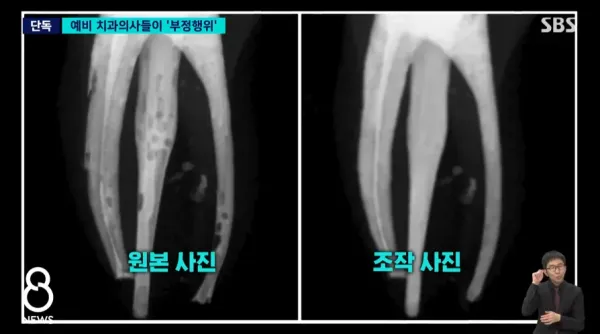

신경치료 실습 했는데 치료 실패한 학생들이

결과 사진을 포샵으로 주작해서 제출했다 걸림

본과 4학년 59명중 34명이 부정행위 걸렸다고 함